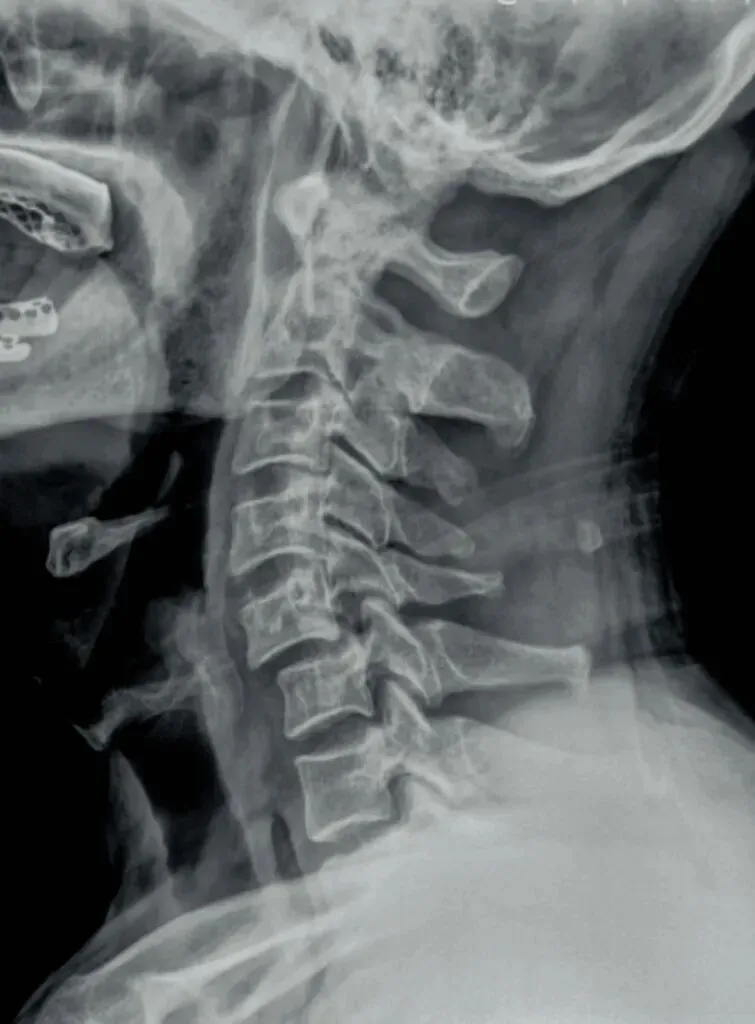

五间是指颈椎椎间隙的变化,主要在颈椎侧位片上观察椎间隙变化同时也反映了椎间盘的变化。

颈椎的退变最早发生在C56椎间盘上,因此C56椎间隙也最早发现变窄的征象。

颈椎骨性椎体为前低后高,

而椎间盘则为前高后低,因此颈椎的生理性前凸是由椎间盘的前高后低所形成的。

在正常情况下,C23、C34和C45间隙大致相等,椎间隙前部为3.8毫米正负0.5毫米,

后缘间隙为1.9毫米正负0.28毫米。

C56间隙较上为宽,而C67间隙最宽,但C7与T1间隙又较窄。